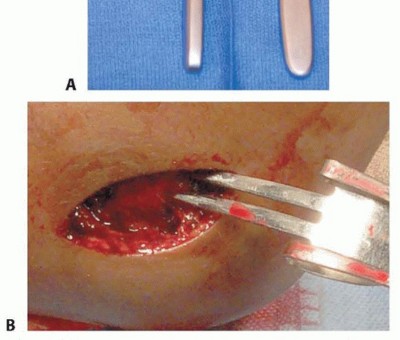

Standard orthopedic equipment includes smooth Kirschner wires (K-wires). For the majority of pediatric patients, 1.6 mm (0.062 inch) wires provide optimal stability, though 2.0 mm (0.078 inch) wires may be required for older adolescents with higher deforming forces. A wire driver, small retractors (such as Senn, Ragnell, or mini-Hohmann retractors), a Freer elevator, and a dental pick or small pointed reduction forceps (tenaculum) must be readily available on the sterile field.

Once the anterior joint capsule is opened, the joint is irrigated copiously with normal saline to remove fracture hematoma and loose cartilaginous debris. The metaphyseal fracture edge on the intact humeral shaft is identified and cleared of interposed periosteum, brachialis muscle fibers, or capsular tissue that frequently blocks reduction.

Reduction is achieved by manipulating the metaphyseal portion of the lateral condyle fragment. A dental pick or a small Freer elevator can be used to gently "joystick" the fragment into position. Alternatively, a small pointed reduction forceps can be applied with one tine carefully placed on the anterior metaphysis of the fragment and the other on the intact humeral shaft.

Closure

The wound is irrigated copiously. The periosteum and deep fascia are meticulously repaired over the fracture site with absorbable sutures. This fascial closure is critical; it prevents muscle herniation and provides a vital secondary layer of stability to the fracture construct. The subcutaneous tissue is closed with interrupted absorbable sutures, and the skin is closed with a running subcuticular stitch or interrupted sutures.

The K-wires can be bent and cut outside the skin to facilitate easy removal in the outpatient clinic, or they can be cut short and buried beneath the skin to theoretically reduce the risk of pin tract infection. The choice depends on surgeon preference, institutional protocol, and the reliability of the patient's family regarding cast care and hygiene.